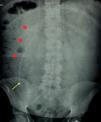

Since the first report in 1954, abdominal pseudocysts have been recognized as a particularly uncommon complication of ventriculoperitoneal shunts of CSF, so their etiology, diagnosis, and therapeutic management remain very controversial.

The clinical presentation of pseudocysts is normally through non-specific abdominal symptoms. The most validated etiology consists on the existence of a concomitant infection of the CSF shunt system, and so, treatment needs of antibiotherapy and total or partial substitution of the system. However, the pseudocyst itself doesn’t need an active treatment, except for some specific cases. This management, algorithmically presented in the present work, achieves a lower recurrence rate than other options, but this one is still important, and is also associated with other complications of those shunts related with several other factors which need to be taken in account.